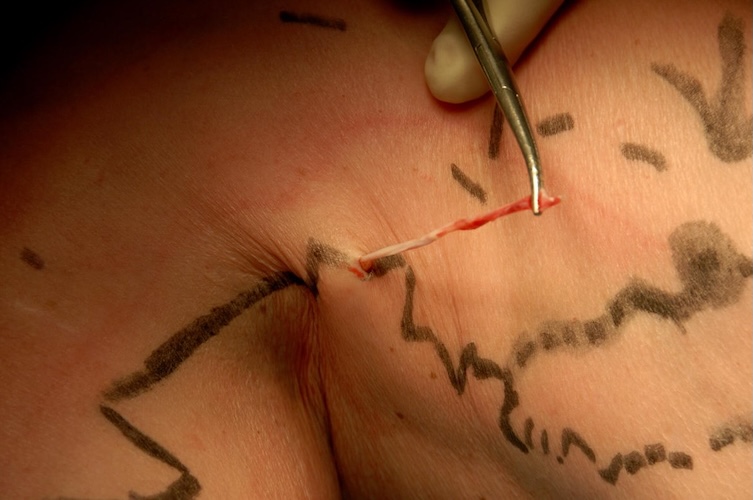

SERVICIO MÉDICO CIRUGÍA VASCULAR

- Especialistas en cirugía vascular y dermatología láser.

- Procedimientos seguros, eficaces y ambulatorios.